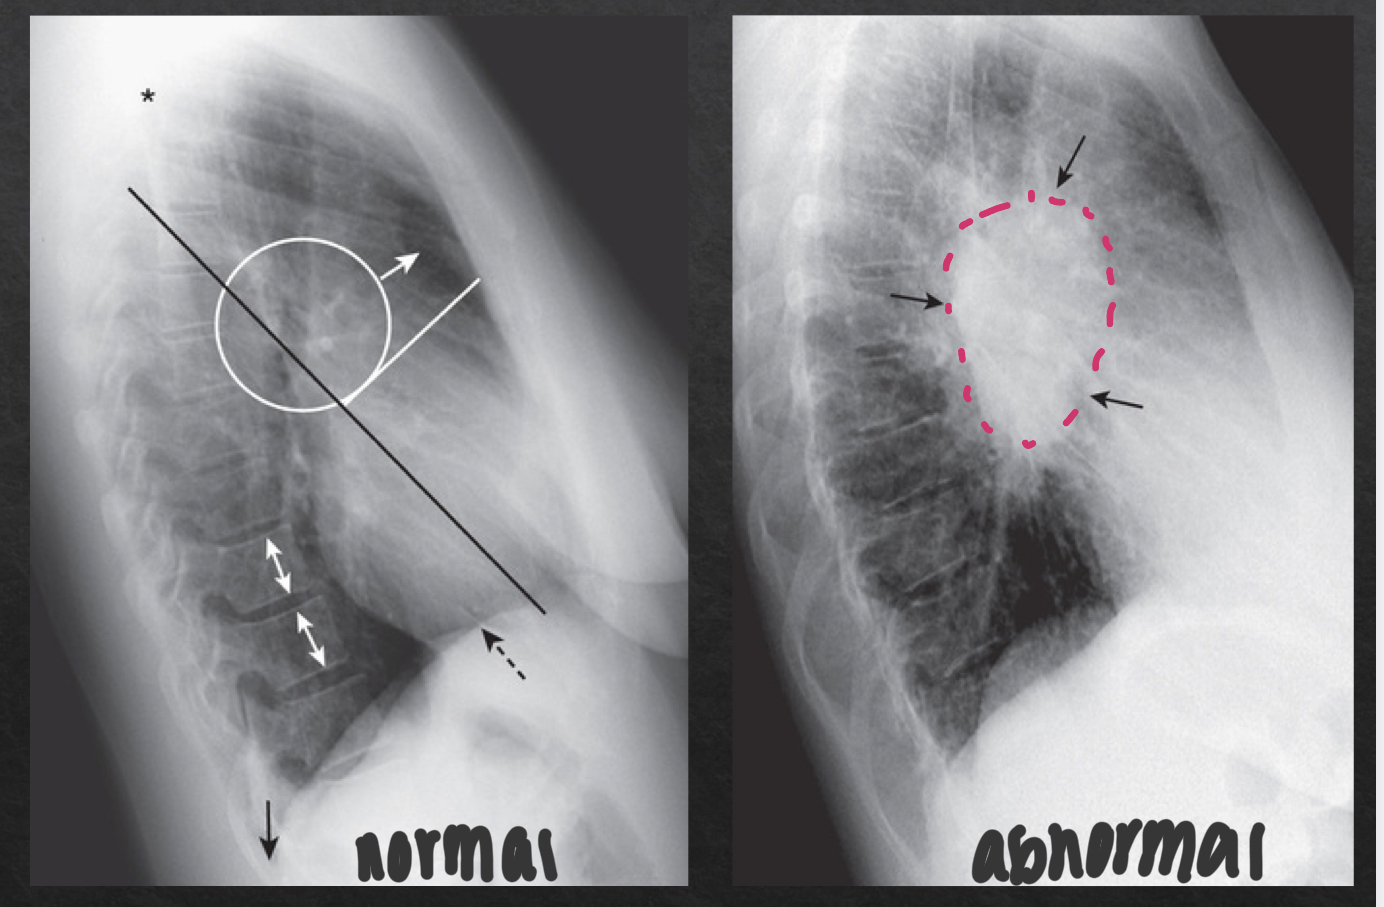

hilar region: lateral view

consists of pulmonary vasculature, pymph nodes, aft, and major bronchi

NORMAL

no discrete mass present

ABNORMAL

distinct, opaque hilar mass

diaphragm and posterior costophrenic sulci: lateral view

sharp posterior costophrenic sulci

R and L hemidiaphragm

R hemi is usually slightly higher and visible for its entire length front to back

L hemi anterior edge usually not visible (silhoueted by heart anteriorly) and posterior edge seen sharply